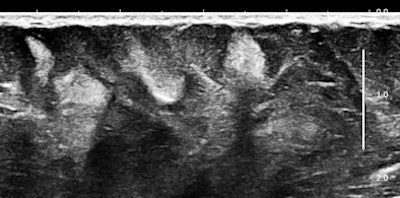

Of course, any of you might say that systemic mastocytosis is such a rare occurrence that one would probably never ever encounter one, but that is probably only true with fully and classically symptomatic cases. We have started looking at abdominal subcutaneous fat as part of our scanning routine, and guess what? This may not be such a rare occurrence at all. Here are some 15-MHz abdominal wall images of a 63-year-old hypothyroid woman who previously had a hysterectomy for a precancerous endometrial polyp:

Her history was interesting, with allergies that began in middle age and episodes of flushing during the past five years that she attributed to "hot flashes."

Soft, well-demarcated reflective nodules in subcutaneous fat are an Aunt Minnie of a sign. They are not palpable, and I suspect they can only be found by high-frequency ultrasound, which is perfect for outpatient screening applications. There may be a completely unexpected, relatively high prevalence of this finding, and it seems that multiple nodules may predispose several allergic disorders, including conditions such as irritable bowel syndrome (IBS), fibromyalgia, and possibly even exercise-induced asthma or postexertional hypotension and reactive tachycardia.

Some of you might think these nodules look like occasional findings in breast ultrasounds that are commonly thought to be lipomas. Lipomas are encapsulated fat, and they are distinguished from fat mainly by their capsular boundary. Here is another type of echogenic nodule, a solid mass of mixed histology with fat, muscle, and vascular components. This type of mass is typically palpable; their firmness is demonstrated by shear-wave elastography:

The first example is of an infiltrating, multifocal process, such as with leukemia; the second involves stable islands of cells without a supporting macrostructure; and the third is a solid, benign mass. The image features are distinct.